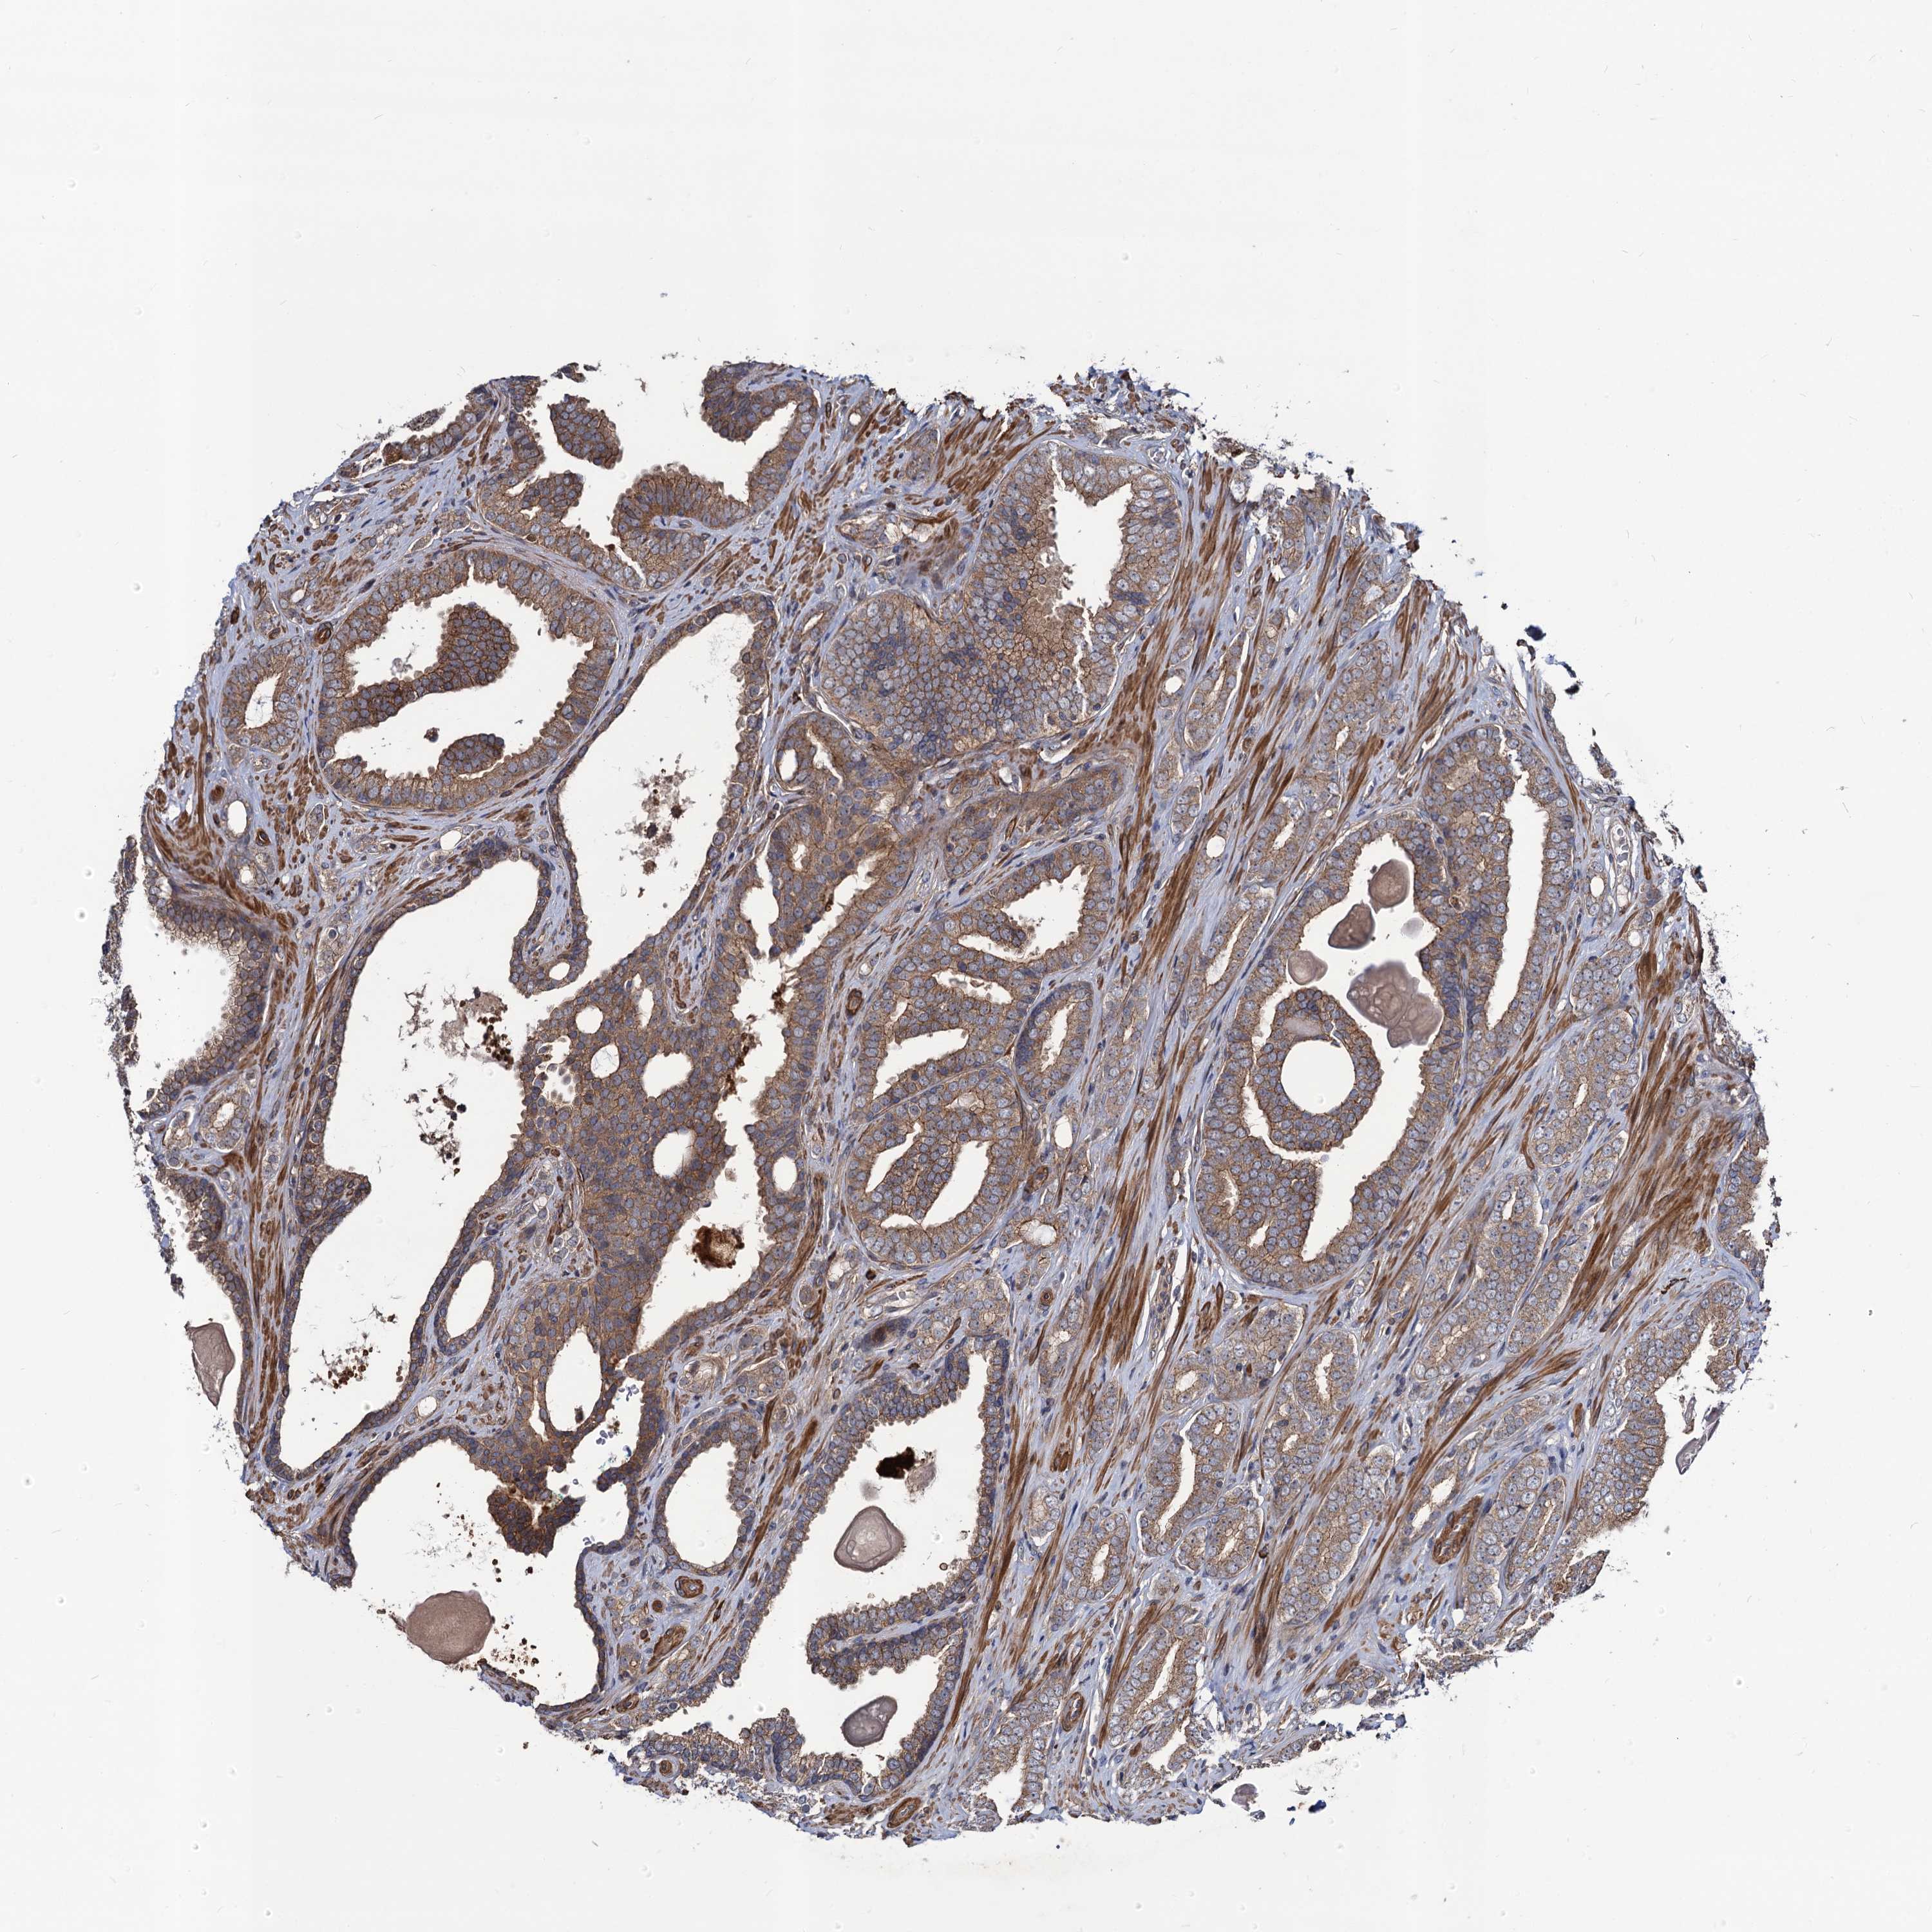

PROSTATE CANCER - Protein expressioni

A mouse-over function shows sample information and annotation data. Click on an image to view it in a full screen mode. Samples can be filtered based on level of antibody staining by selecting one or several of the following categories: high, medium, low and not detected. The assay and annotation is described here.

Antibody stainingi

Antibody staining in the annotated cell types in the current human tissue is reported as not detected, low, medium, or high, based on conventional immunohistochemistry profiling in selected tissues. This score is based on the combination of the staining intensity and fraction of stained cells.

Each image is clickable and will lead to virtual microscopy that enables deeper exploration of all samples and also displays staining intensity scores, fraction scores and subcellular localization as well as patient and tissue information for each sample.

Antibody HPA041507

Antibody HPA041599

Staining

High

Medium

Low

Not detected

Intensity

Strong

Moderate

Weak

Negative

Quantity

>75%

75%-25%

<25%

None

Location

Nuclear

Cytoplasmic/membranous

Cytoplasmic/membranous,nuclear

Adenocarcinoma, High grade

Adenocarcinoma, Low grade

Adenocarcinoma, NOS